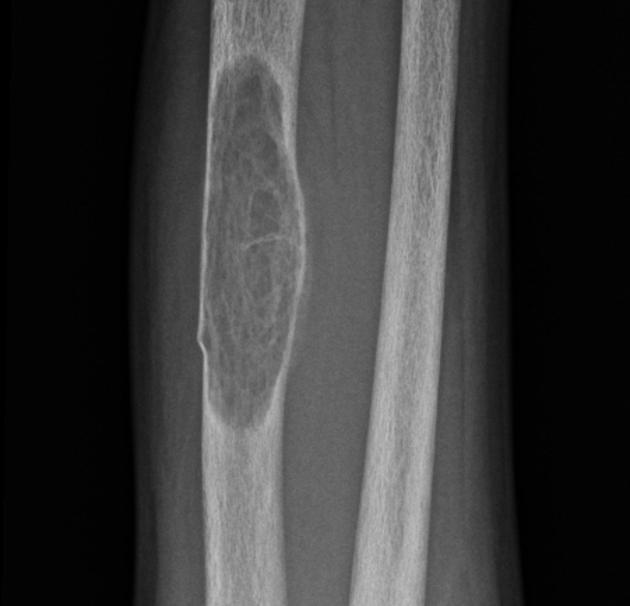

4) Brown tumors. Expansile well-defined geographic lytic lesions with narrow zone of transition. (mandible, hands, pelvis, ribs)